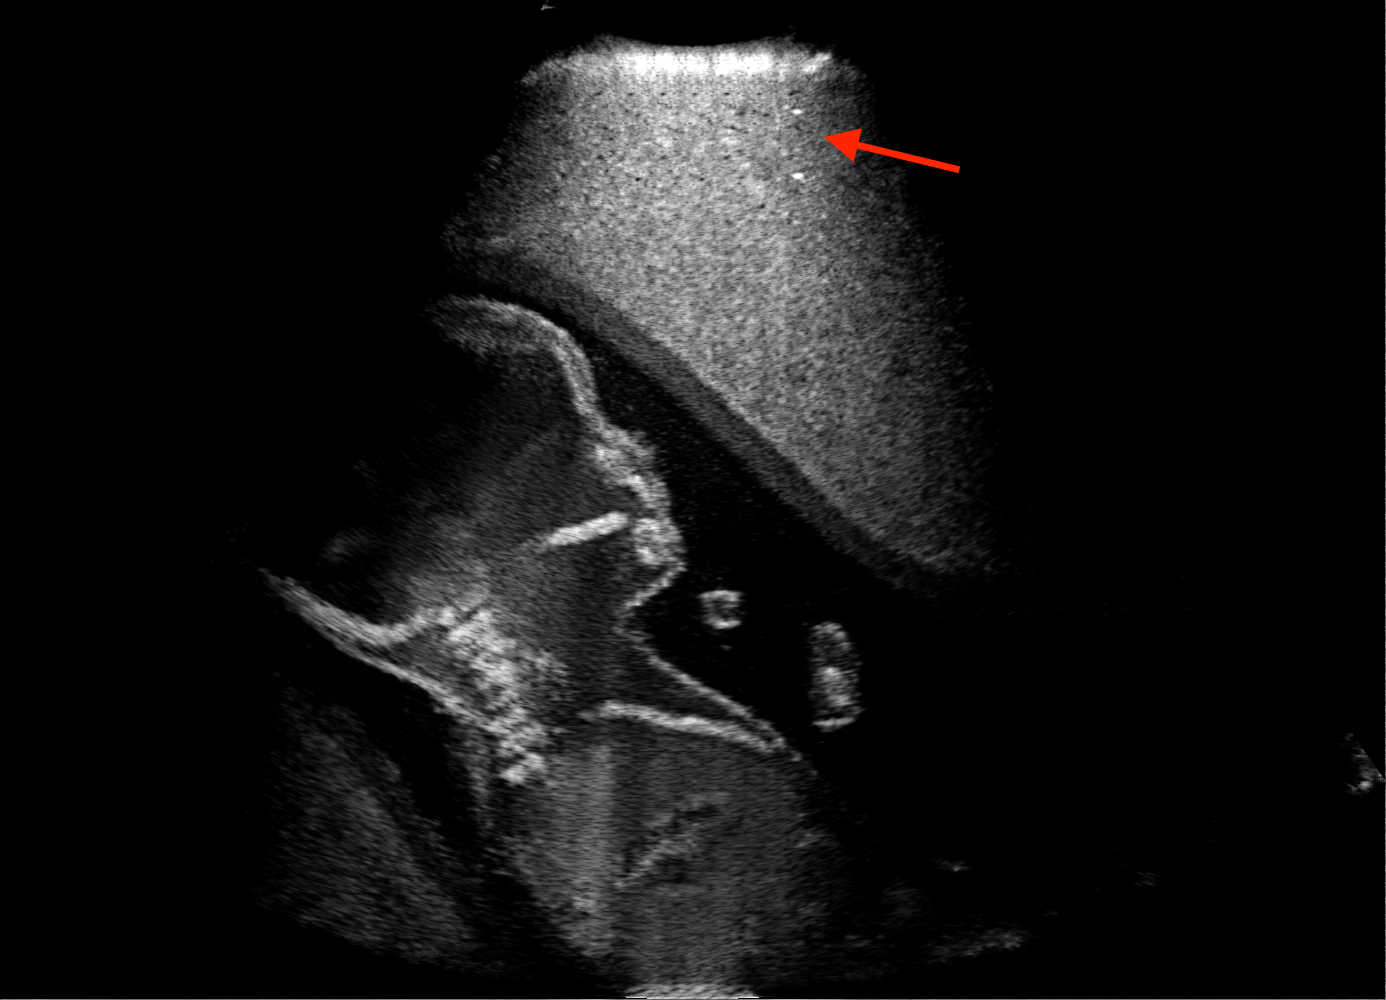

For the interpretation of the local errors, sample spatial p error maps are depicted in Fig. 3 for LSA2H, NSA2H, and SA2H for the middle two examples shown in Fig. 2. Both images generated by NSA2H have a lot of missing structures and accordingly have high error almost all over the map. Artificial skull enhancement with LSA2H is seem to evoke large p error, as shown in the corresponding error map, whereas the bright spots in the error map of SA2H reflect some hallucinated shadows and structure in the brain. All of above mentioned regions of interest are marked by red arrows. In the bottom example, SA2H fails to generate faithful content at the bottom region marked by red circles, which is well indicated by the error map as well.